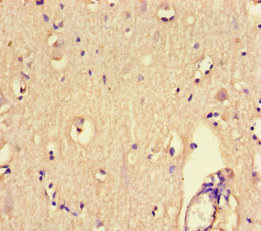

Immunohistochemistry of paraffin-embedded human brain tissue using CSB-PA613393LA01HU at dilution of 1:100